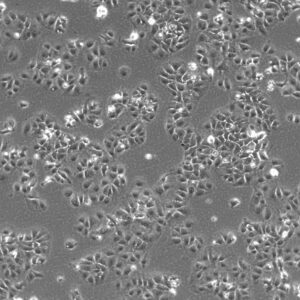

Morphology: Epithelial-like

Growth Properties: Adherent

Description: HuH7 was established in 1982 by Nakabayashi et al. from a 57-year-old Japanese male with well differentiated hepatocellular carcinoma.